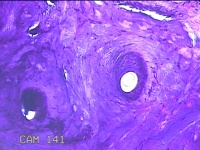

右手臂伸侧肿物

性别

女

年龄

27岁

临床诊断

纤维瘤病

一般病史

下腹部坠胀三天。

标本名称

大体所见

灰褐色肿物0.5x0.3x0.2cm一个,表面糜烂。

图4